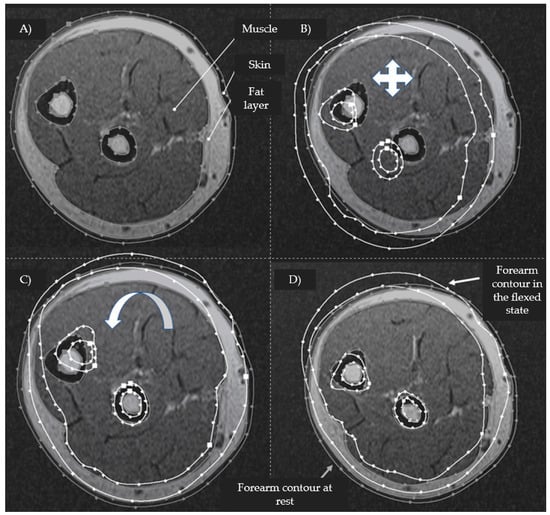

2.4. Parametric Assessment of Morphological Changes in Forearm Tissues When Performing Hand Actions Based on MRI